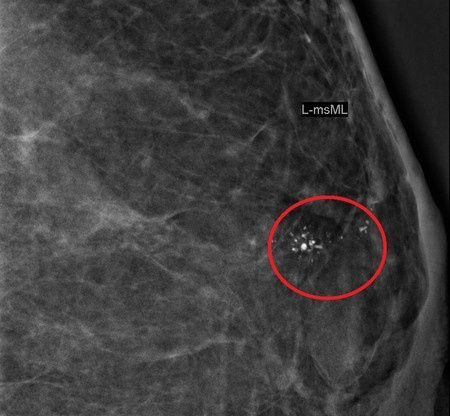

钼靶上的一小簇钙化有时候也可能是早期的乳腺癌